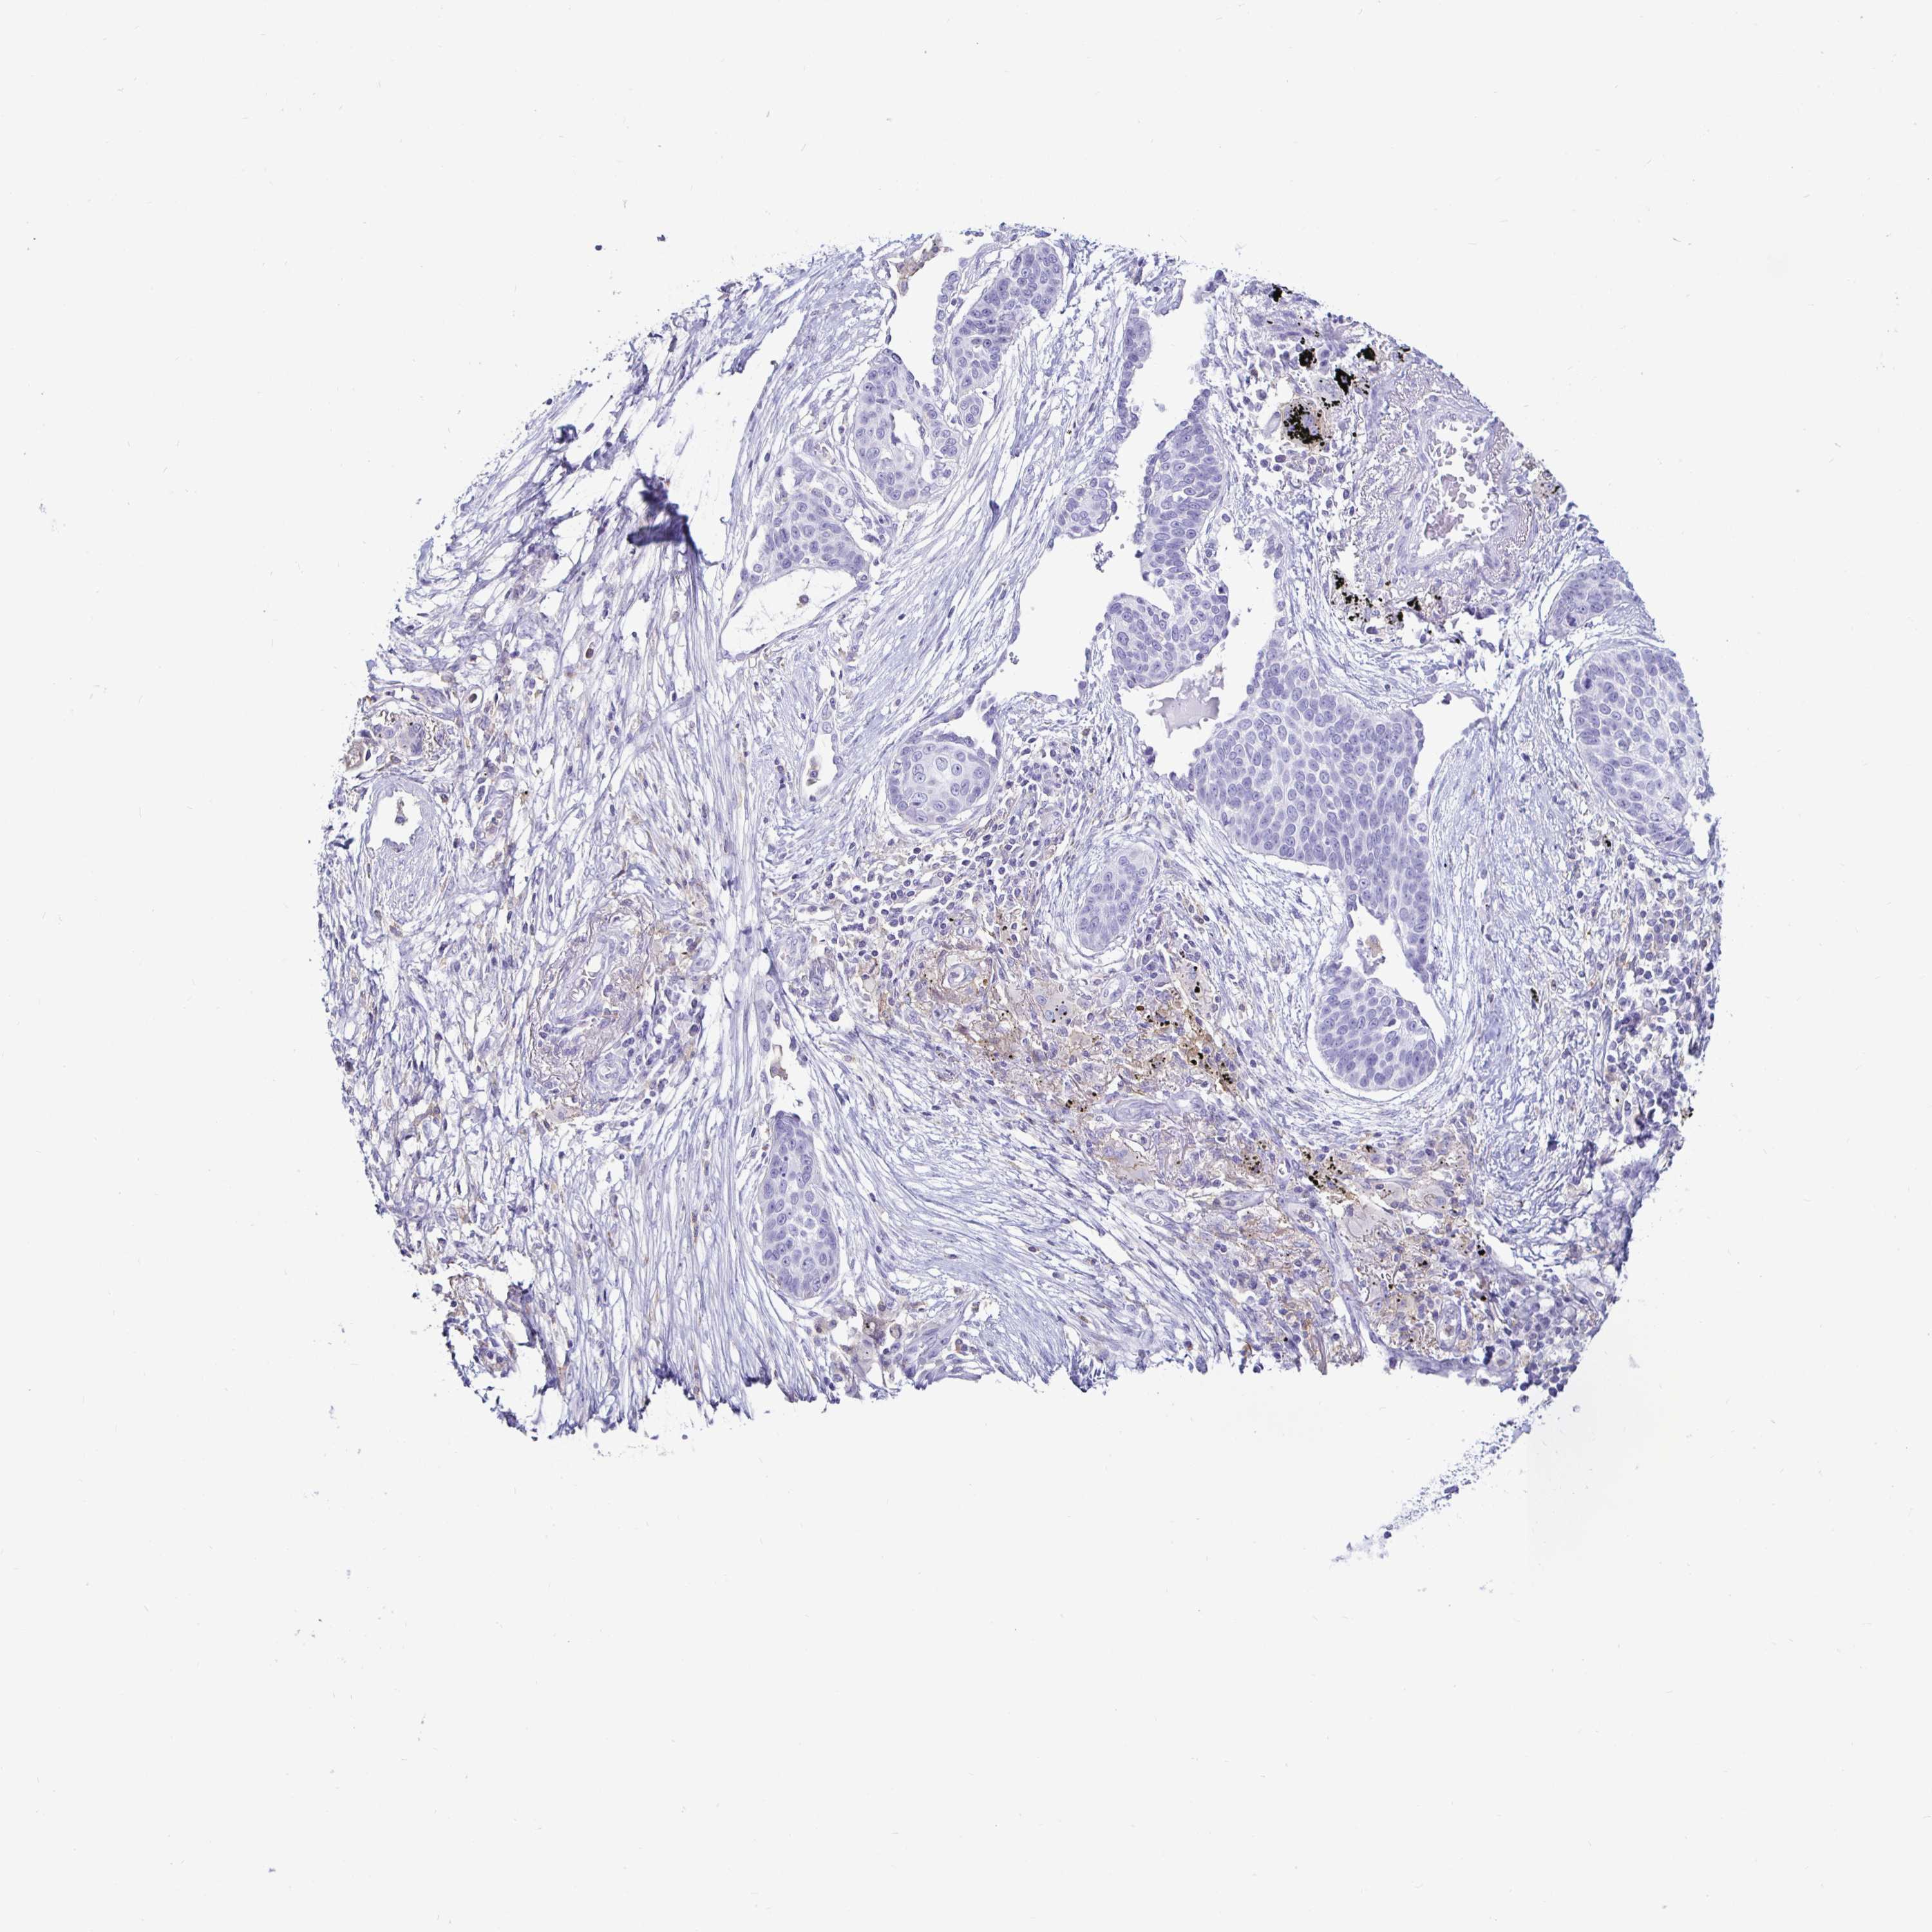

CANCER LUNG CANCER Show tissue menu

LUAD TCGA LUAD VALIDATION LUSC TCGA LUSC VALIDATION PROTEIN LUAD CPTAC PROTEIN LUSC CPTAC PROTEIN EXPRESSION